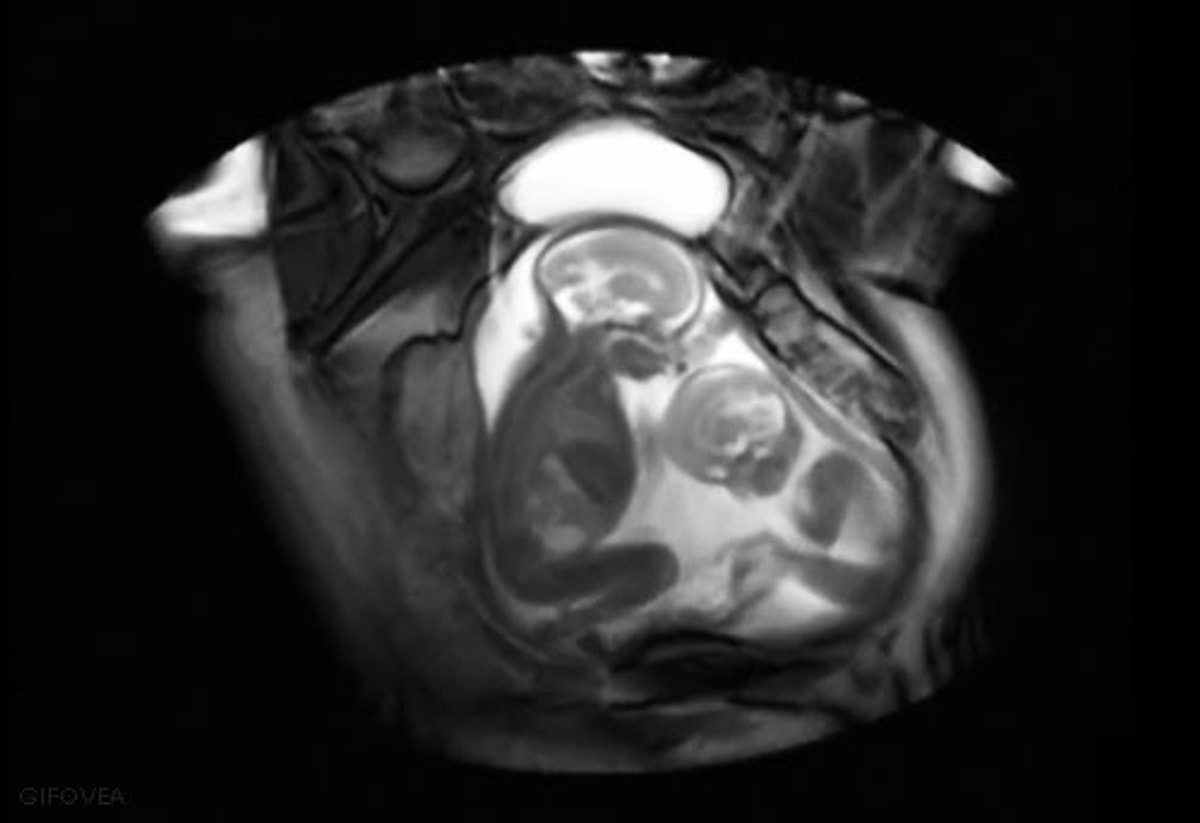

Чрево утроба

Чрево утроба 112 фото